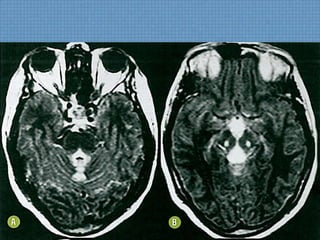

INTOXICAÇÃO POR CO

INTOXICAÇÃO SUICIDA-3H

• Hemorragia Palidal aguda bilateral;

DIFUSÃO

TC-ACHADOS SEQUELAS

INTUITO SUICIDA 3 ANOS ANTES

ACHADOS DE IMAGEM

• TC sem contraste:

– Hipoatenuação simétrica palidal;

• RM:

– Hipossinal em T1 palidal simétrico, podendo apresentar

realce periférico ou pontual pelo gadolíneo;

– Hiperssinal em T2/FLAIR em topografia medial de globos

pálidos  Isquemia ou Edema Vasogênico?

– Restrição à difusão indica irreversibilidade do dano neuronal;

– Cronicamente, lesões sequelares mostram-se com

hiperssinal em T2/FLAIR;